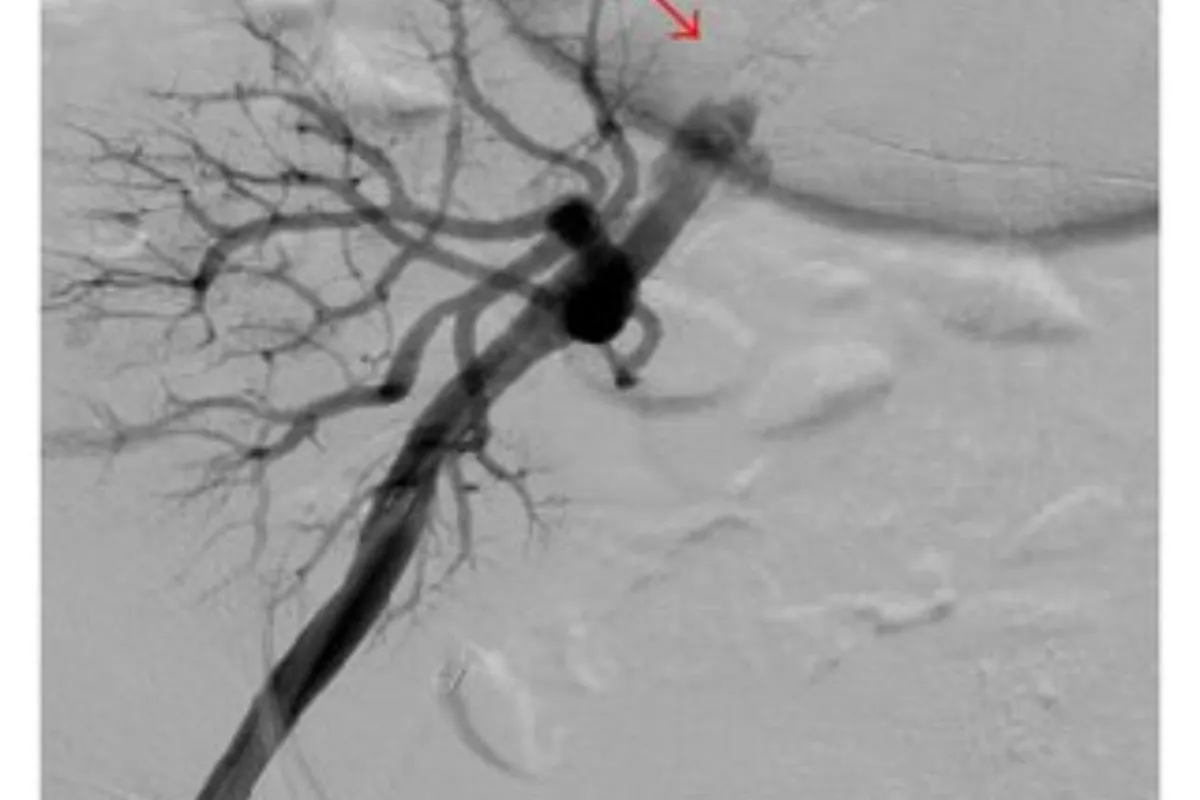

Peripheral Angioplasty procedure at Sarda Vascular Centre Dehradun

Interventional Radiology (IR) uses real-time imaging such as X-ray, ultrasound, CT, or MRI to guide tiny instruments through the body for treatment — without large surgical incisions.